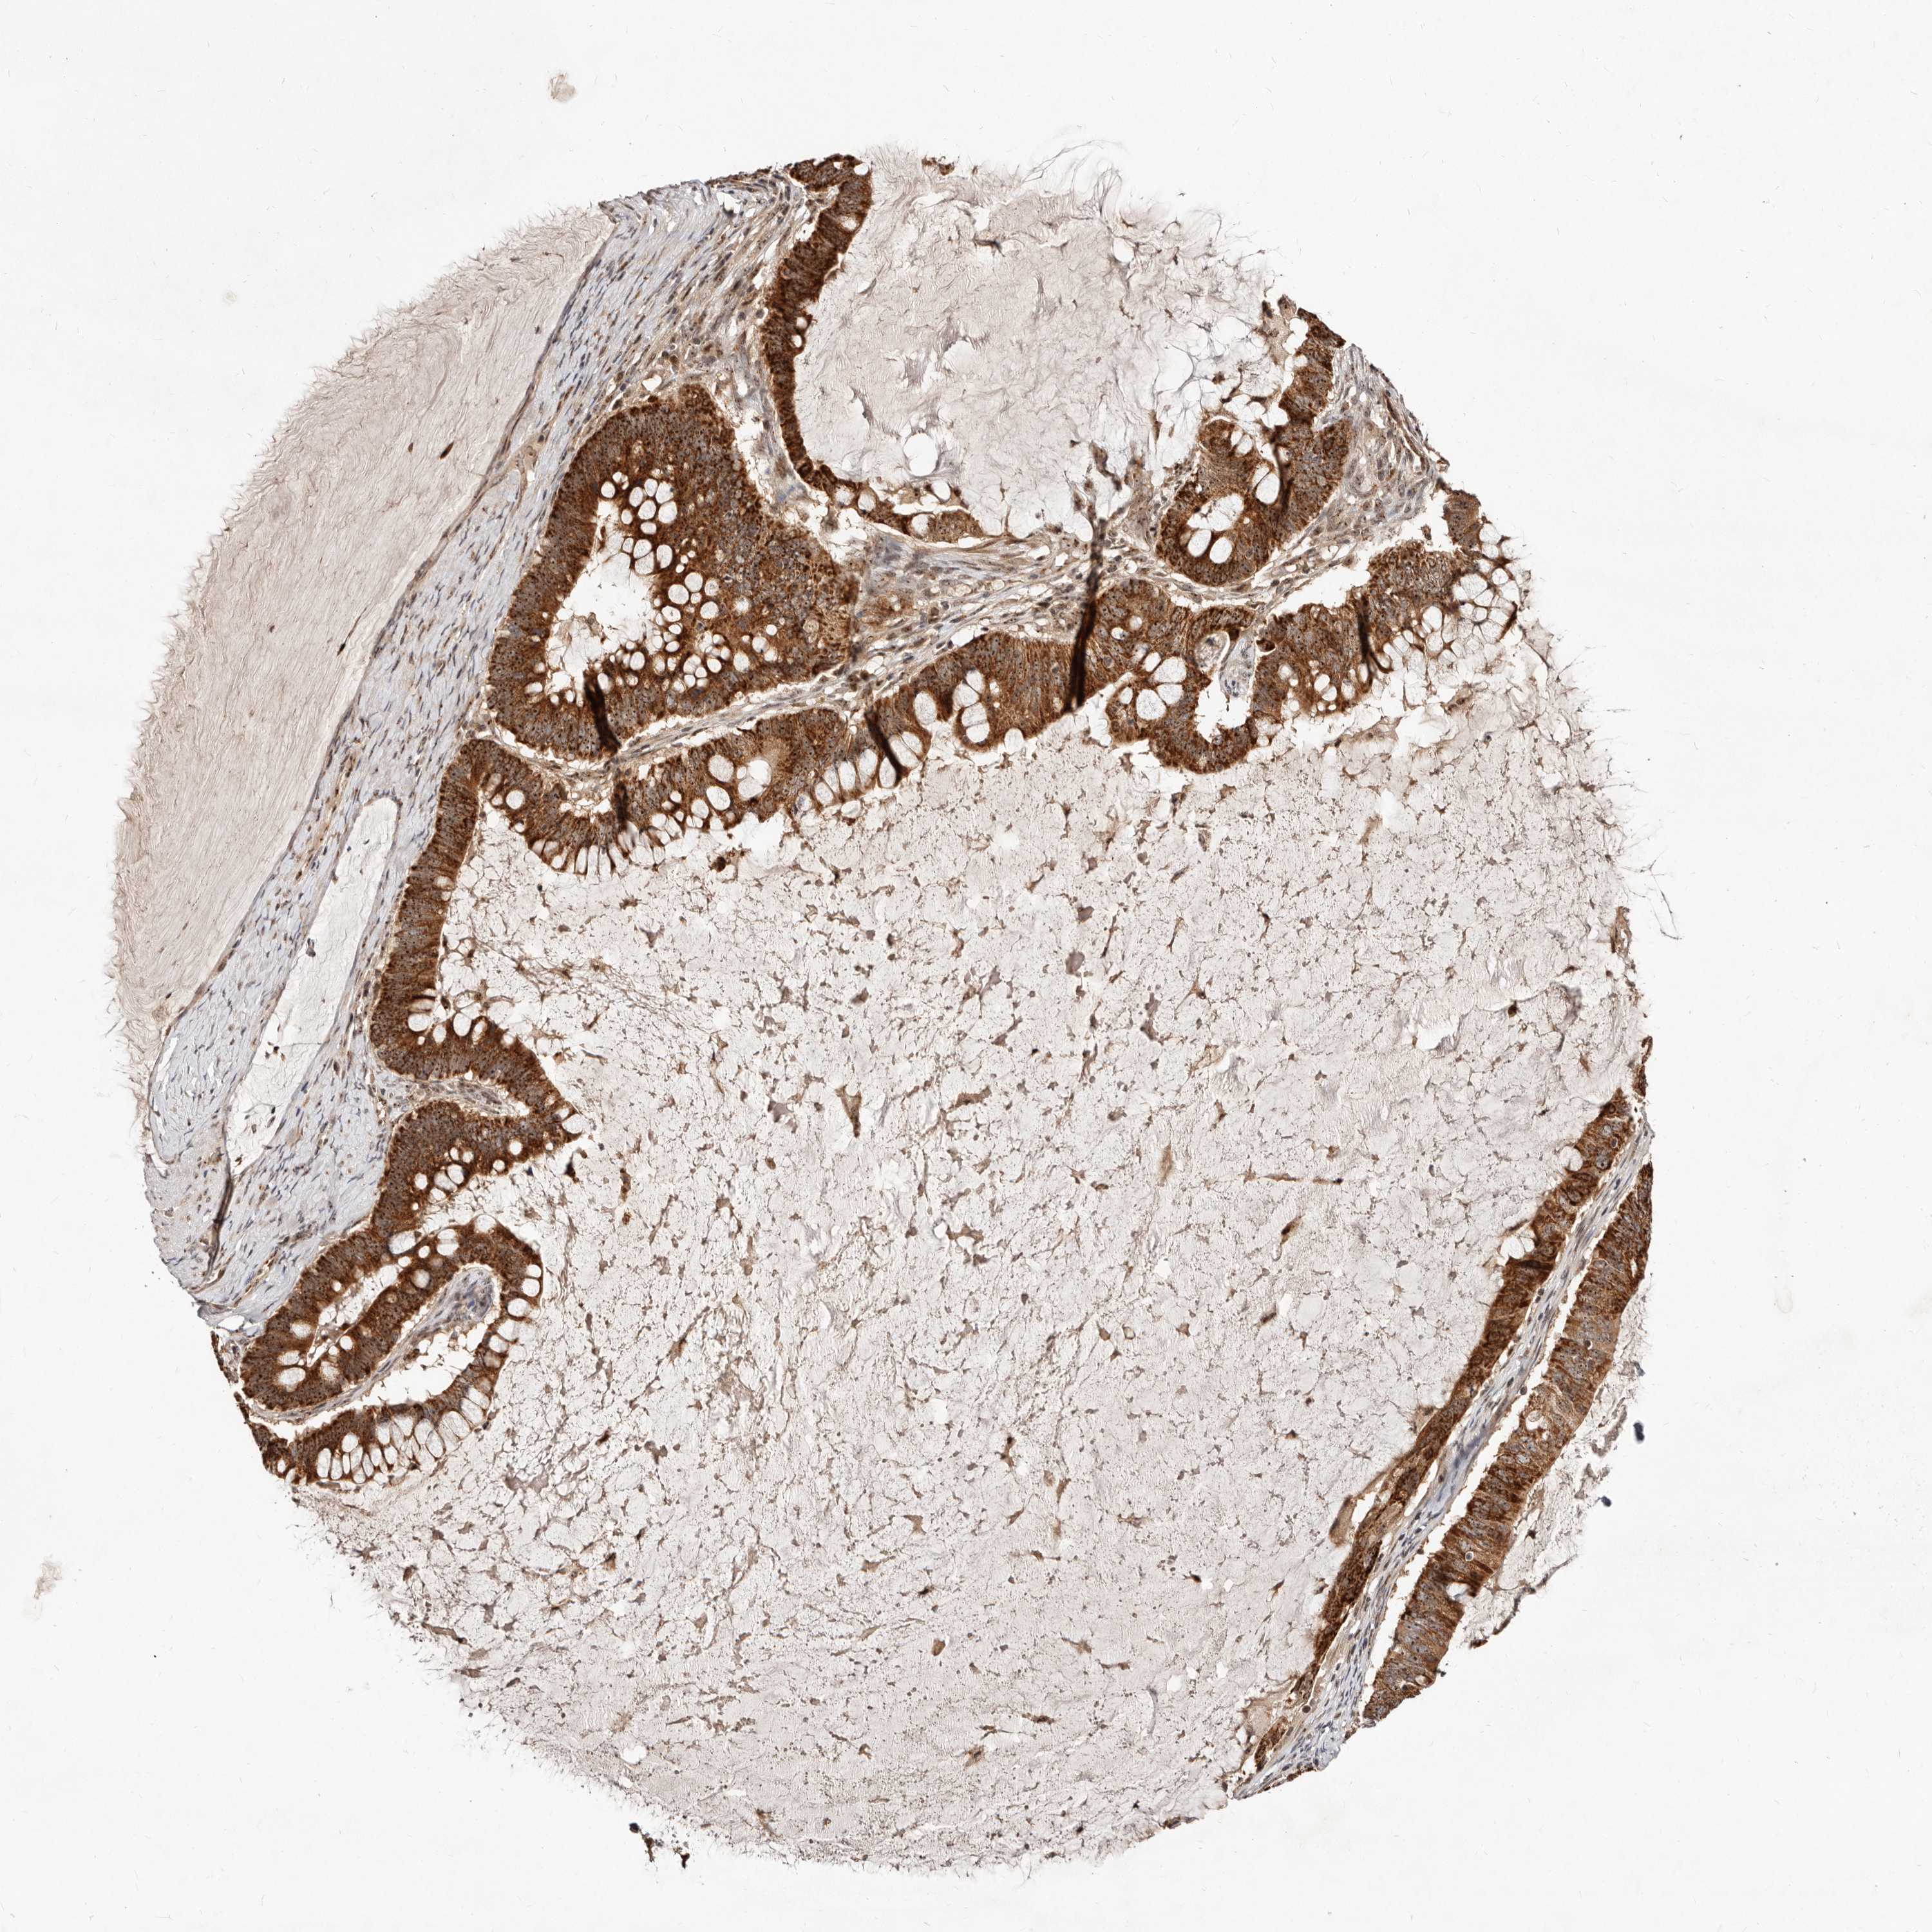

OVARIAN CANCER - Protein expressioni

A mouse-over function shows sample information and annotation data. Click on an image to view it in a full screen mode. Samples can be filtered based on level of antibody staining by selecting one or several of the following categories: high, medium, low and not detected. The assay and annotation is described here.

Note that samples used for immunohistochemistry by the Human Protein Atlas do not correspond to samples in the TCGA dataset.

Antibody stainingi

Antibody staining in the annotated cell types in the current human tissue is reported as not detected, low, medium, or high, based on conventional immunohistochemistry profiling in selected tissues. This score is based on the combination of the staining intensity and fraction of stained cells.

Each image is clickable and will lead to virtual microscopy that enables deeper exploration of all samples and also displays staining intensity scores, fraction scores and subcellular localization as well as patient and tissue information for each sample.

Antibody HPA029165

Antibody HPA029167

Antibody CAB028574

Cystadenocarcinoma, serous, NOS